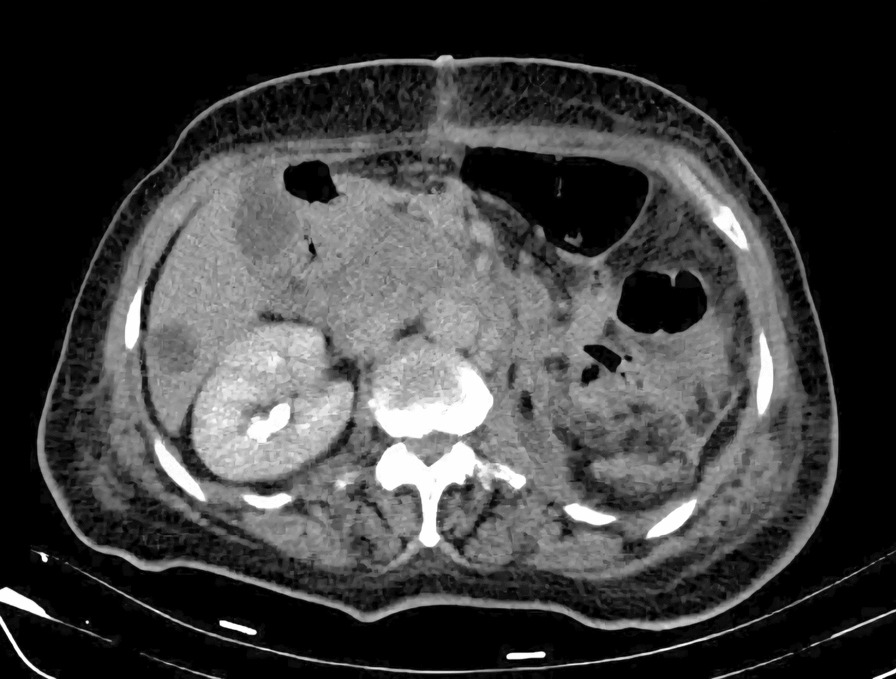

Fig. 8.

Postoperative computed tomography

The ICV is free of thrombus, but there are already developed regional and liver metastases.

On the follow-up computed tomography (CT) scan performed one month after surgery, the inferior vena cava was free of tumor, but unfortunately, the tumor had already spread to the liver and retroperitoneum (Fig. 7). The patient’s condition deteriorated 3 months after surgery and despite aggressive chemotherapy, she passed away 6 months later. Owing to religious reasons, no autopsy was performed.